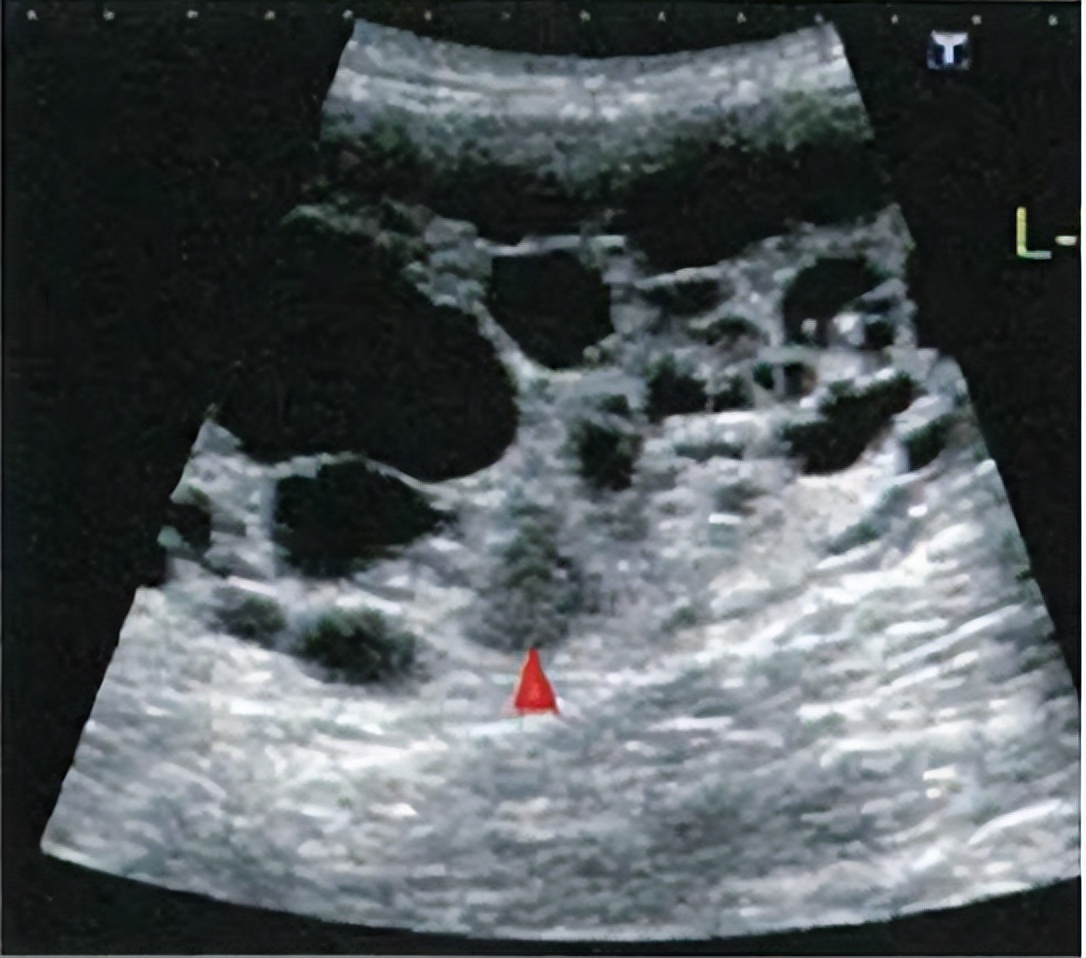

B超显示下的多囊肾☝